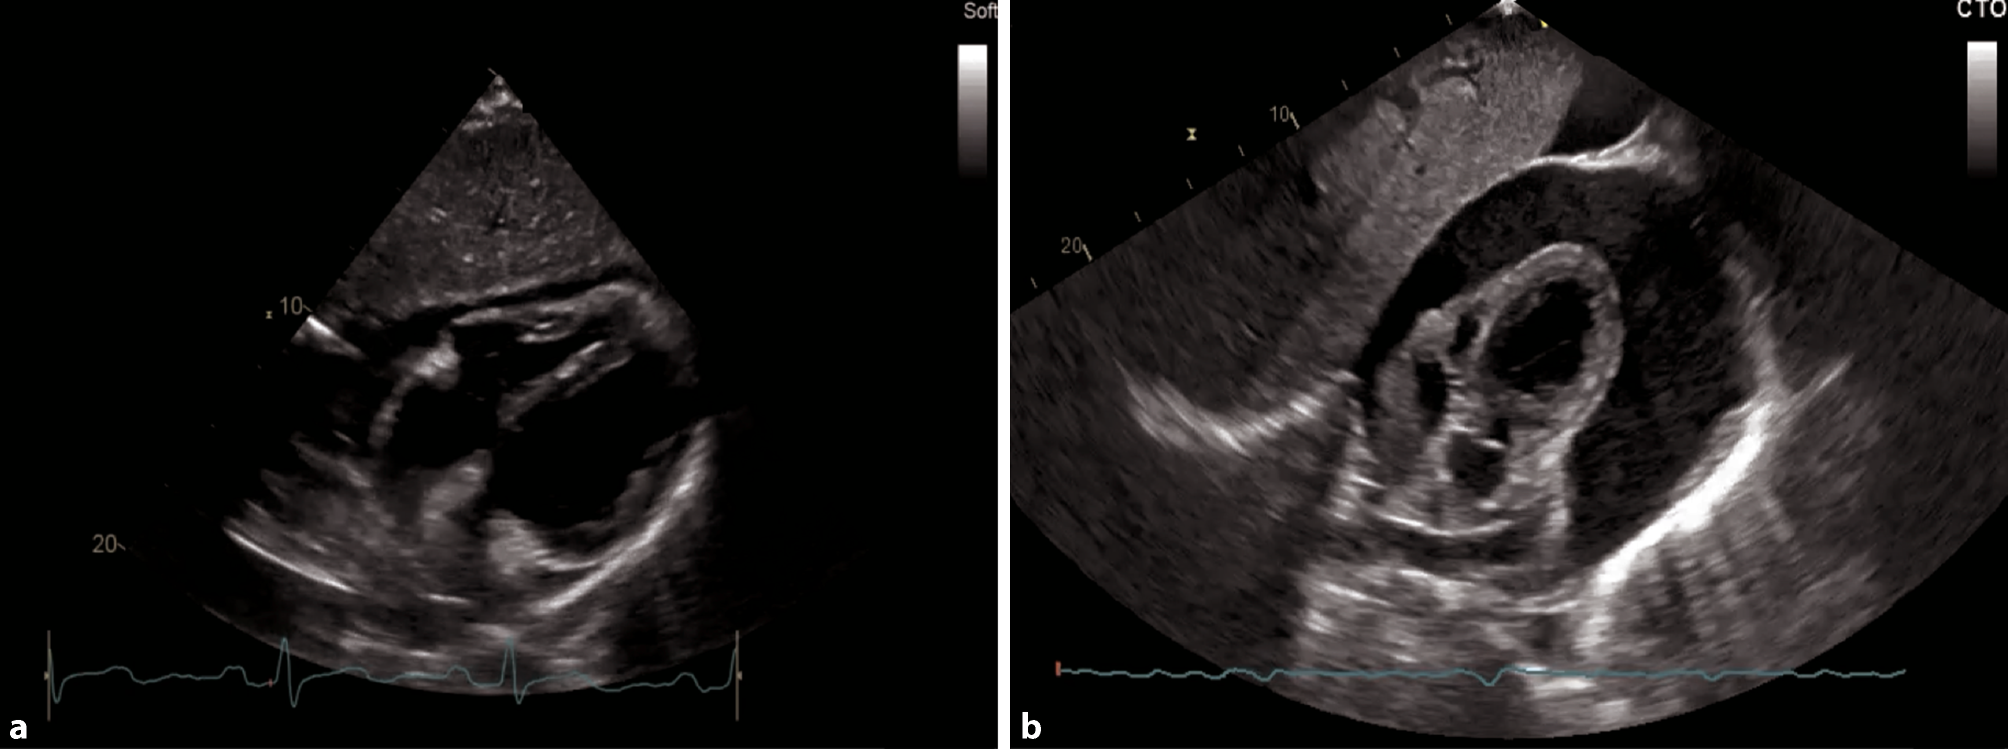

Fig. 13

Apical 4‑chamber view (4‑ChV). a Schematic of a 4-ChV. RV right ventricle, TV tricuspid valve, RA right atrium, LV left ventricle, LA left atrium, AMVL anterior mitral valve leaflet, PMVL posterior mitral valve leaflet. b 2D image of an apical 4‑ChV

A comprehensive examination can be achieved with various views; however, in acute and intensive care settings, a subcostal 4‑chamber view (subcostal 4‑ChV) should be utilized as it provides a lot of information and is easiest to achieve in a supine patient as well. If imaging from a subcostal approach is not possible, alternative views can be chosen, such as a parasternal long axis view (PLAX) or an apical 4‑chamber view (4-ChV) (Figs. 11, 12 and 13).